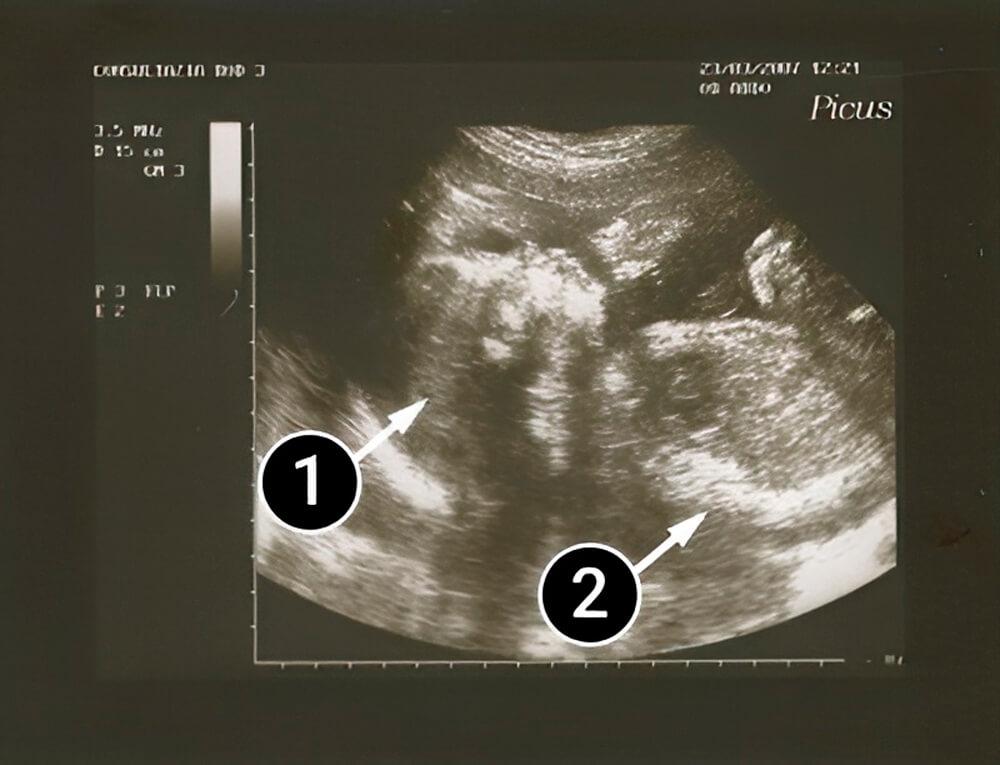

¿Qué se puede ver en la ecografía/ultrasonido?

En esta imagen, un bebé está acostado boca arriba y su perfil es visible con una frente, nariz y mentón bien definidos. También se puede ver su mano derecha.